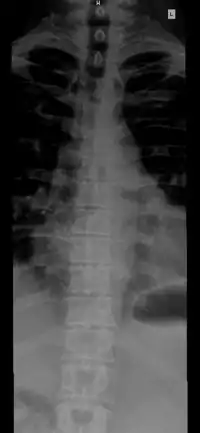

Позвоно́чный столб, или позвоно́чник (columna vertebralis) — основная часть осевого скелета человека. Состоит из 32-34 позвонков, последовательно соединённых друг с другом в вертикальном положении[1][2]. Позвонки разделяют на отдельные типы: шейные, грудные, поясничные, крестцовые (срастаются в крестец) и копчиковые.

«#» — шейный отдел (Pars cervicalis)

«#» — грудной отдел (Pars thoracalis)

«#» — поясничный отдел (Pars lumbalis)

«#» — крестец (Os sacrum)

«#» — копчик (Os coccygis)